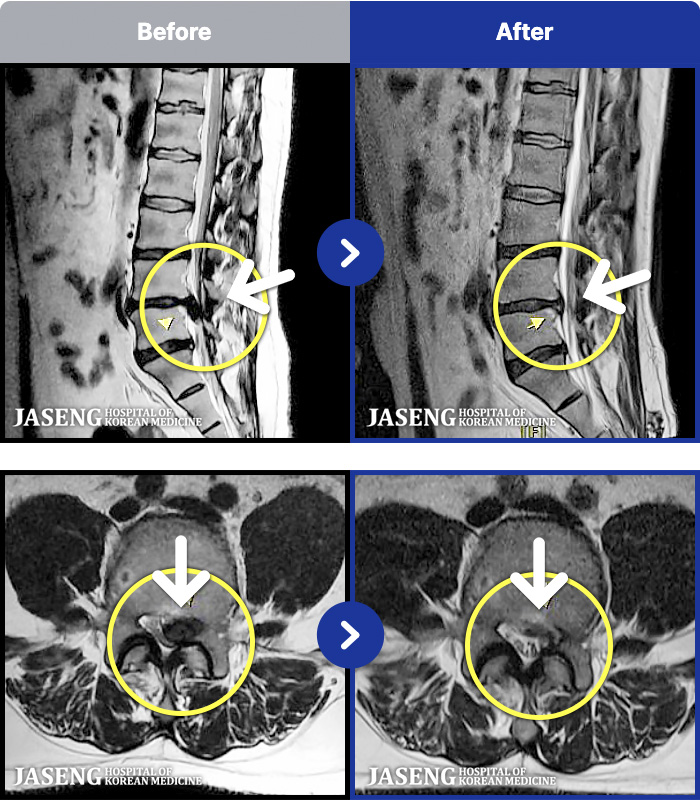

94 MRI ũ ʸ Ȯϼ.

MRI ġ

Ƹ ϰ ־.

[õ] 25.03.18~25.07.22

ȯںп Ǹ ǿ ԿǾ, ο ġ ۿ Ƿ ġḦ Ͻñ ٶϴ.